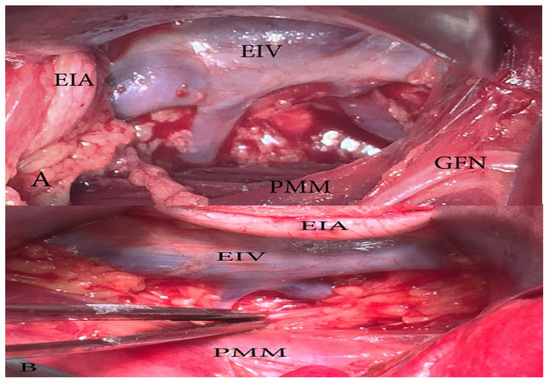

- Genitofemoral nerve identification. Lateral incision to the fascia of the psoas muscle is preferable in order to avoid genitofemoral nerve injury. The nerve is located lateral to the external iliac vessels and sometimes overlying them.

19.3. Genitofemoral Nerve (GFN) Anatomy

19.4. The GFN Variations Related to PLNDGO